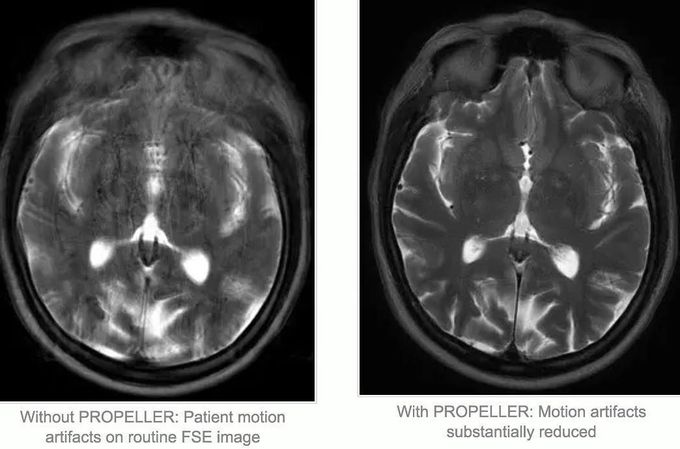

How does PROPELLER (BLADE, MultiVane) reduce motion artifacts? PROPELLER technique has the advantage of central k-space oversampling, so that image artifacts (motion, flow etc) are greatly reduced.